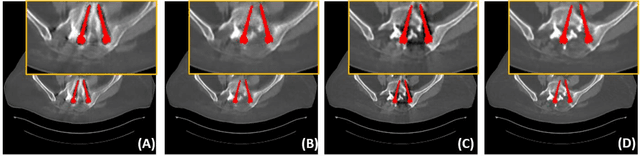

Abstract:Due to the presence of metallic implants, the imaging quality of computed tomography (CT) would be heavily degraded. With the rapid development of deep learning, several network models have been proposed for metal artifact reduction (MAR). Since the dual-domain MAR methods can leverage the hybrid information from both sinogram and image domains, they have significantly improved the performance compared to single-domain methods. However,current dual-domain methods usually operate on both domains in a specific order, which implicitly imposes a certain priority prior into MAR and may ignore the latent information interaction between both domains. To address this problem, in this paper, we propose a novel interactive dualdomain parallel network for CT MAR, dubbed as IDOLNet. Different from existing dual-domain methods, the proposed IDOL-Net is composed of two modules. The disentanglement module is utilized to generate high-quality prior sinogram and image as the complementary inputs. The follow-up refinement module consists of two parallel and interactive branches that simultaneously operate on image and sinogram domain, fully exploiting the latent information interaction between both domains. The simulated and clinical results demonstrate that the proposed IDOL-Net outperforms several state-of-the-art models in both qualitative and quantitative aspects.

Abstract:Metal implants can heavily attenuate X-rays in computed tomography (CT) scans, leading to severe artifacts in reconstructed images, which significantly jeopardize image quality and negatively impact subsequent diagnoses and treatment planning. With the rapid development of deep learning in the field of medical imaging, several network models have been proposed for metal artifact reduction (MAR) in CT. Despite the encouraging results achieved by these methods, there is still much room to further improve performance. In this paper, a novel Dual-domain Adaptive-scaling Non-local network (DAN-Net) for MAR. We correct the corrupted sinogram using adaptive scaling first to preserve more tissue and bone details as a more informative input. Then, an end-to-end dual-domain network is adopted to successively process the sinogram and its corresponding reconstructed image generated by the analytical reconstruction layer. In addition, to better suppress the existing artifacts and restrain the potential secondary artifacts caused by inaccurate results of the sinogram-domain network, a novel residual sinogram learning strategy and nonlocal module are leveraged in the proposed network model. In the experiments, the proposed DAN-Net demonstrates performance competitive with several state-of-the-art MAR methods in both qualitative and quantitative aspects.